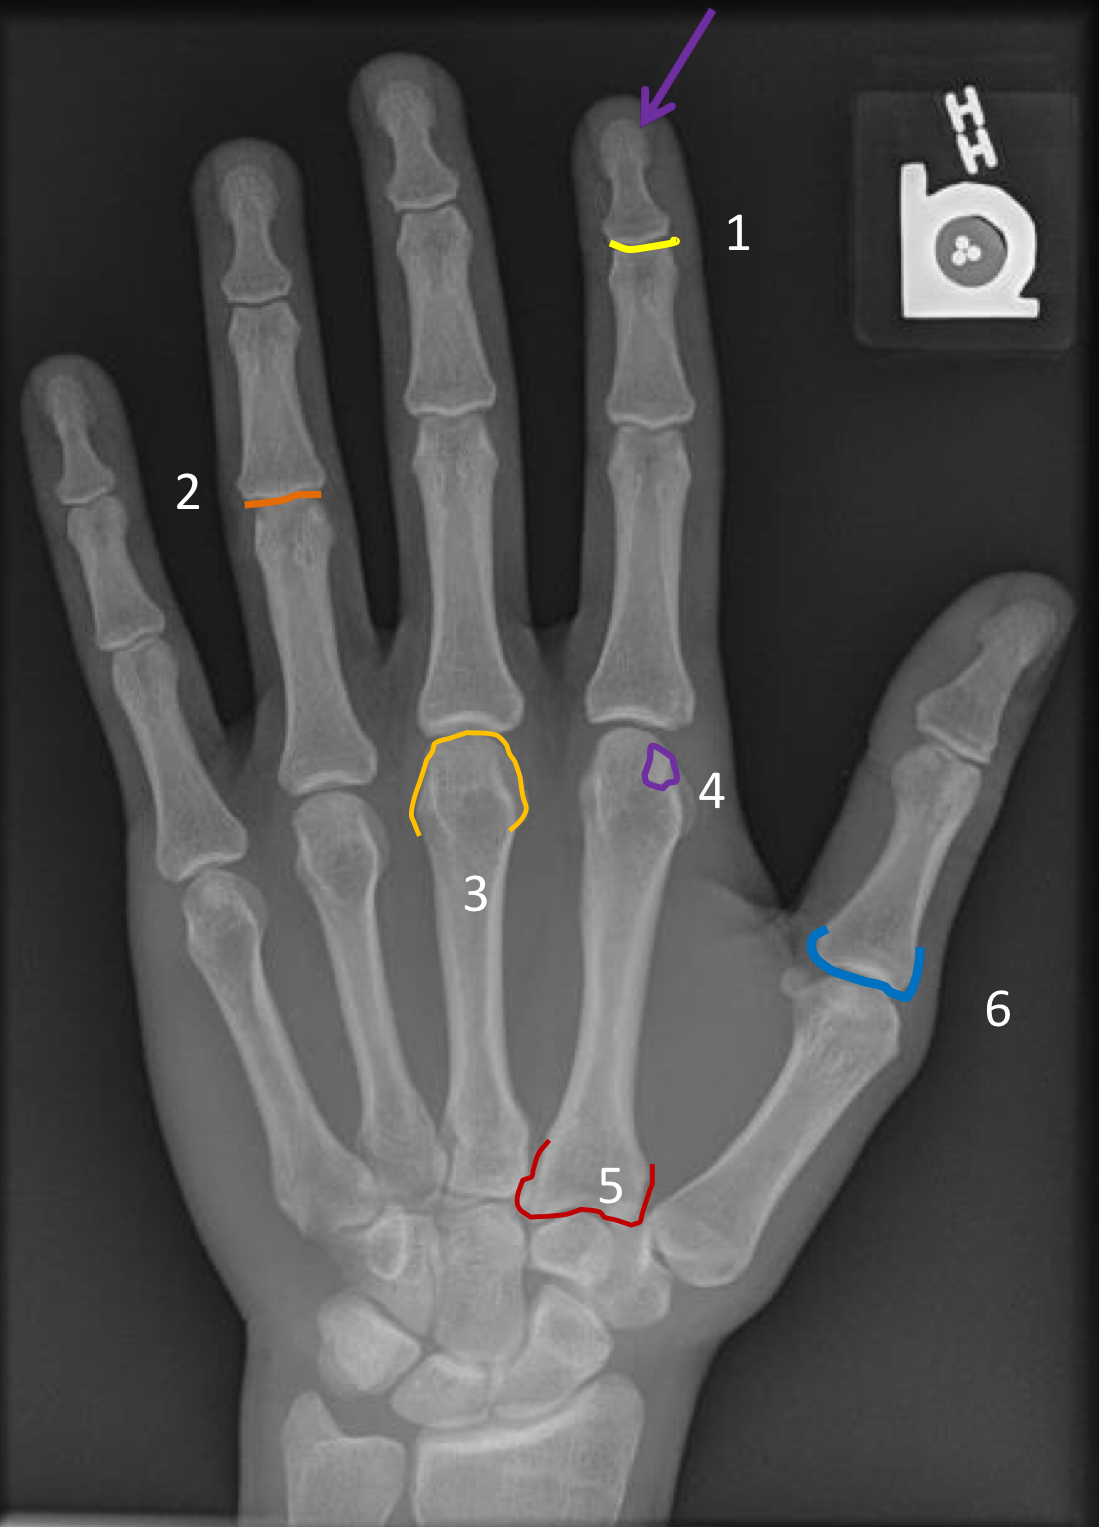

What view is this?

PA hand

purple arrow?

ungual tuft

1?

distal interphalangeal joint of the 2nd digit

2?

4th proximal interphalangeal joint

3?

head of 3rd metacarpal

4?

sesamoid of 2nd metacarpophalangeal joint

5?

base of 2nd metacarpal

6?

base of 1st proximal phalanx